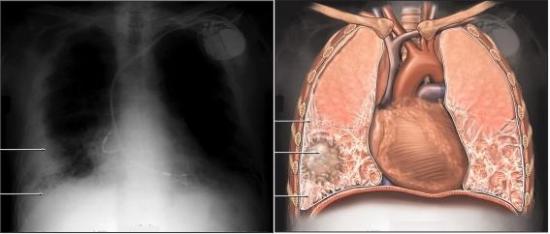

肺组织纤维化(图)